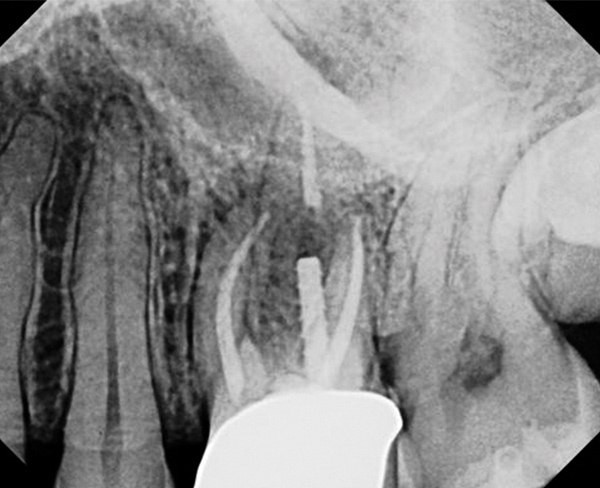

CBCT can be used to aid in further assessment of a previously endodontically treated tooth. A study by Uraba et al demonstrated that CBCT imaging is 20% more effective in detecting periapical lesions that cannot be detected on a periapical radiograph (Figure 1 and Figure 2).7 Diagnostic CBCT can provide additional information in comparison to periapical radiographs when treatment planning an endodontic retreatment case.8 The use of a limited field of view (FOV) CBCT on a patient that presents with a problem on an existing endodontically treated tooth can allow the clinician to critically evaluate the quality of the existing canal(s) obturation, identify any missed canals, and assess the extensiveness of a periapical lesion.

CBCT of the same tooth N o. 14 (palatal

view exposure) shown in Fig 1 definitively shows a periapical lesion.

Fig 2.